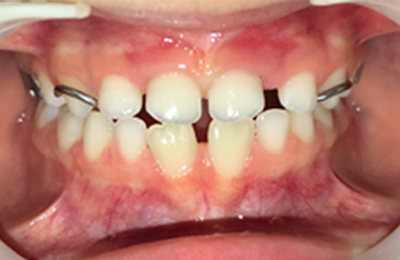

Caso 1

As imagens abaixo ilustram um caso de mordida cruzada anterior tratado com ortopedia facial. Observe que os incisivos superiores, que se encontravam inicialmente atrás dos incisivos inferiores, passou a ocluir corretamente.